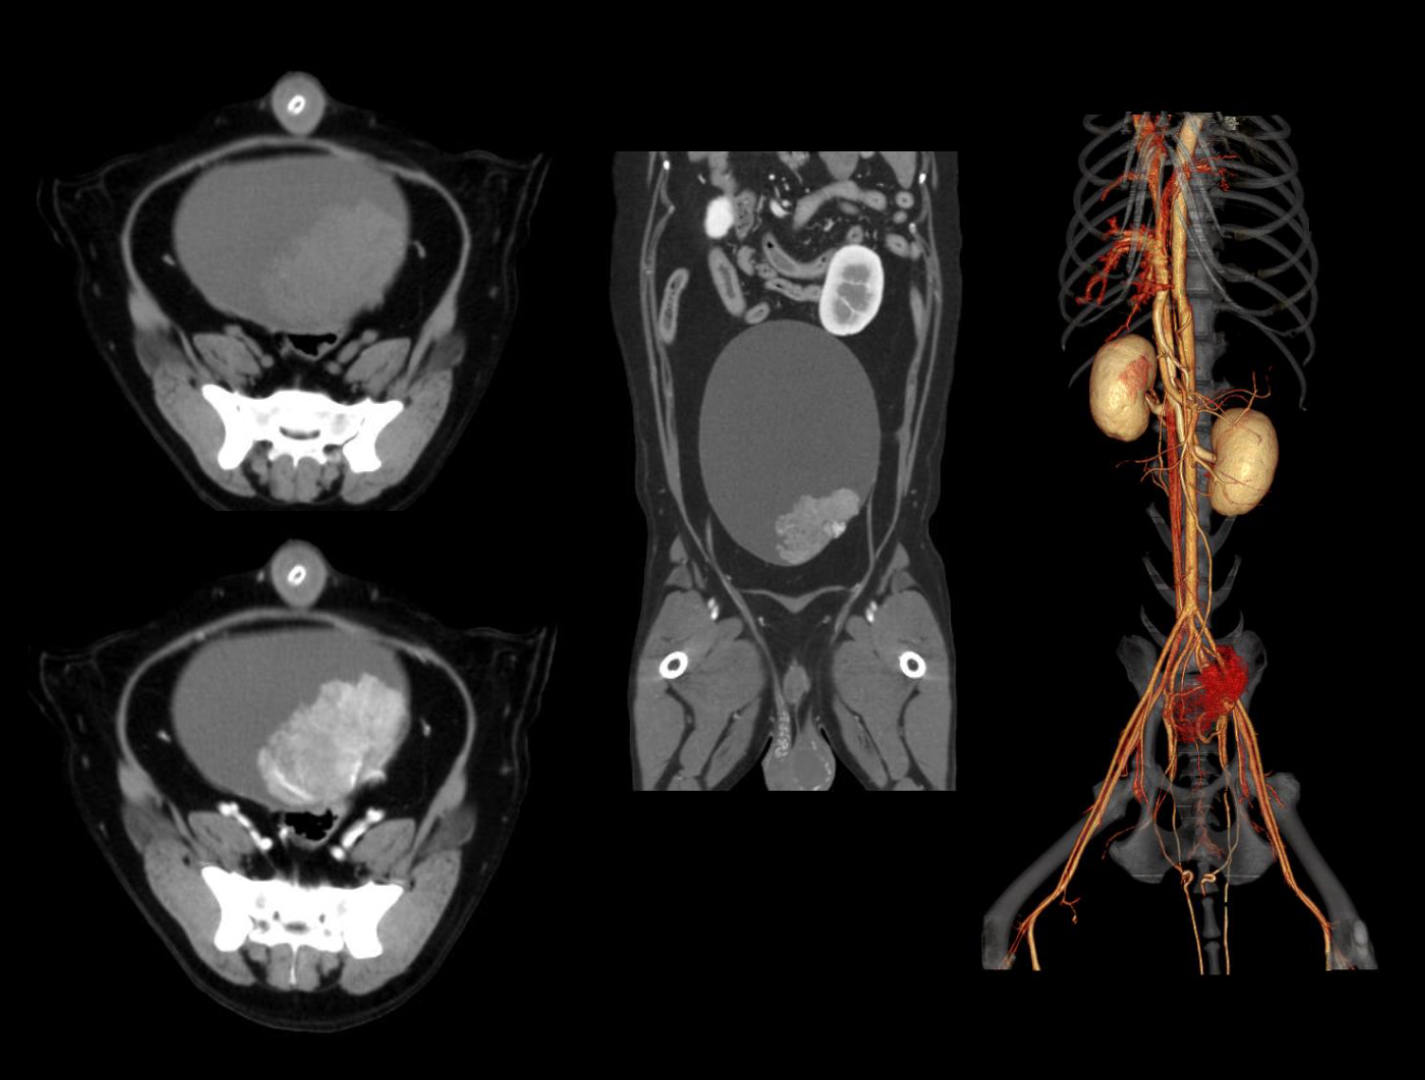

урология

онкология и хирургия

SinoVision AlphaCT 358 Plus — компьютерный томограф на 64 среза. Устройство позволяет получать изображения высокой чёткости с помощью современной интеллектуальной платформы.

Универсальный томограф AlphaCT 358 Plus позволяет получать изображения высокой чёткости.

Удобная работа с контрастным веществом благодаря функции инициации начала сканирования при достижении заданной плотности контрастированной крови по шкале Хаунсфилда.

• Интеллектуальная система обработки изображения

• Патентованный детектор V-PIXEL